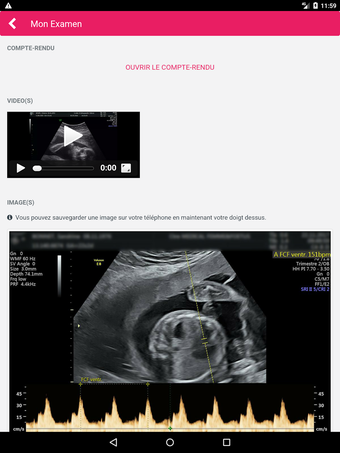

MediFile is an application for medical professionals to manage all of their ultrasound images, reports, and other patient data in one place. The application allows them to scan, view, and save their files directly from their device. The application has the capability to upload reports to the server of the doctor or midwife, for whom the report was sent.

The main advantage of the application is that it makes it very easy for the medical professional to view and share their patient's data with their colleagues. It also facilitates the creation of a patient database and a communication channel for all of the medical professionals working on the same case.